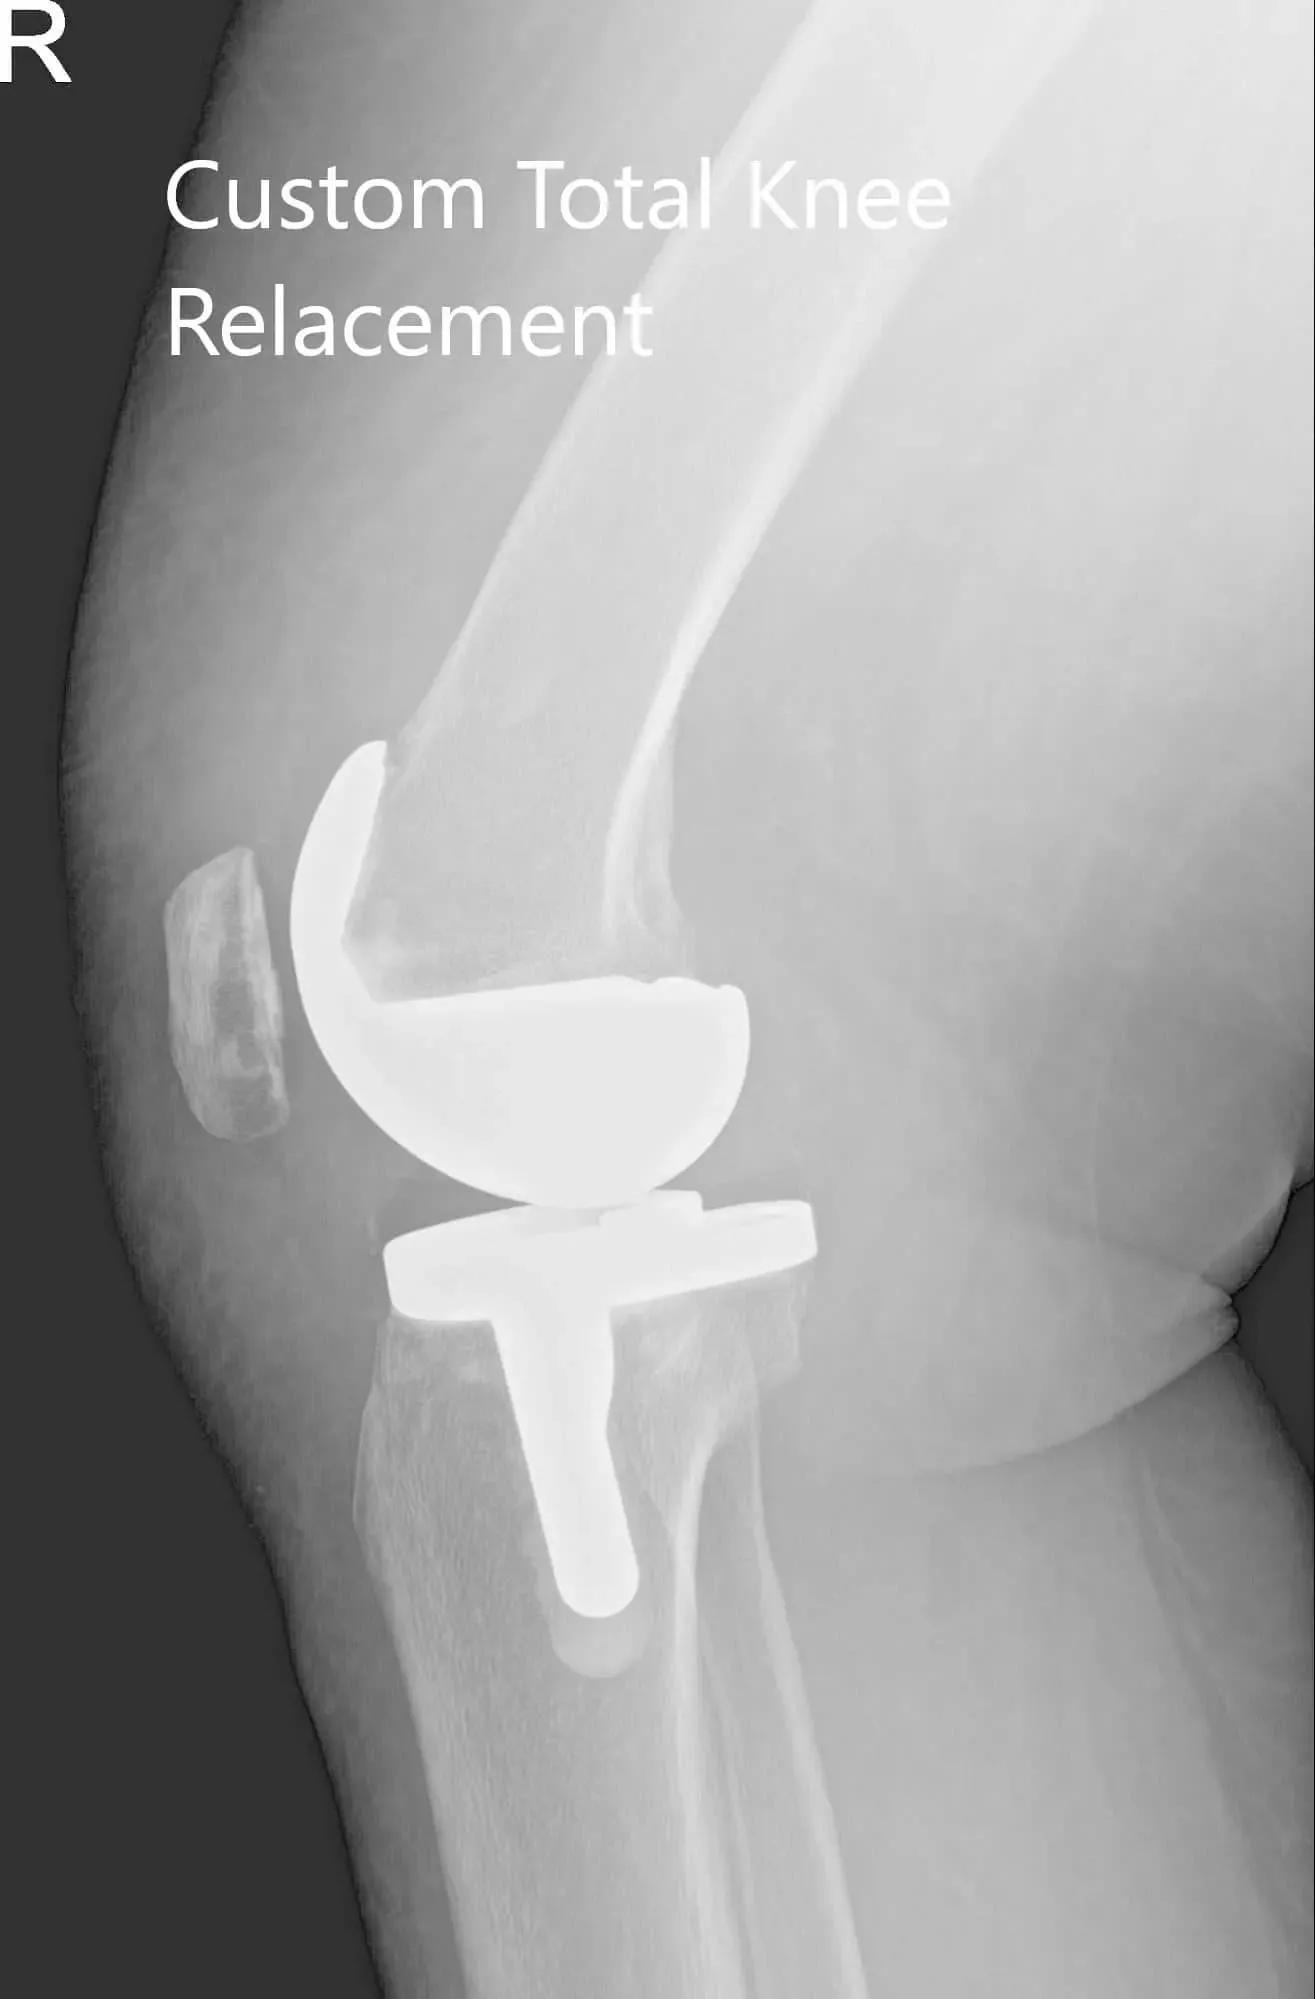

Radiografía postoperatoria de la rodilla derecha del paciente mostrando visión AP y lateral

El paciente pudo soportar peso con apoyo el mismo día de la cirugía. En visitas posteriores, se comprobó que su herida no tenía ninguna infección y se retiraron grapas de la piel tras la cicatrización. Demostró un excelente rango de movimiento de la rodilla en visitas posteriores.

El paciente cumplió con el programa de fisioterapia y ejercicio en casa. Mostró un rango completo de movimiento, que no tuvo dolor en una revisión de 3 meses. Afirmó que podía conducir un coche, subir escaleras y jugar con sus nietos sin la ansiedad de provocar el dolor. El paciente afirmó que experimentó una mejora en la calidad del sueño y pudo retomar su trabajo como agente penitenciario. El paciente ha vuelto ahora a las actividades que disfrutaba antes del proceso de la enfermedad.